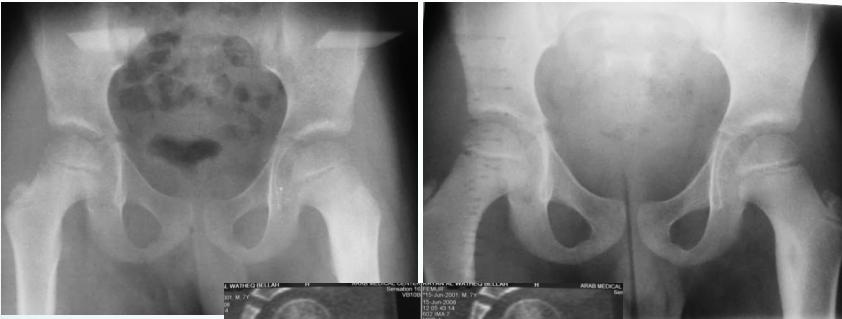

Aneurysmal Bone Cyst

- Child - young adult

- Metaphysis of long bone

- X-ray:

- Well-defined cyst

- Trabeculated

- Eccentrically placed

- Ballooning

- Bloody content

- Treatment:

- Curettage and bone graft

- Metaphysis, Eccentric